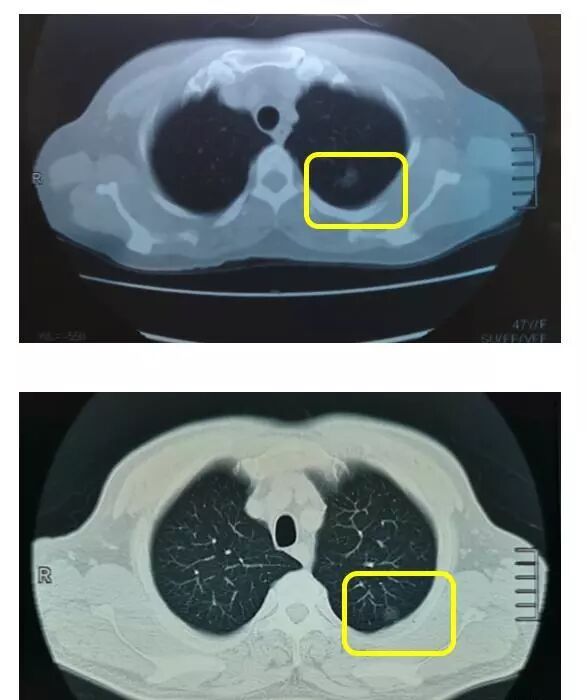

肺癌在临床医学上分为四期,从一期到四期,严重程度不断加重,四期通常叫做“晚期”。 临床很多研究显示,一期肺癌患者的五年存活率可以超过92%,十年存活率也可以高达88%,原位癌患者的治愈率更可达100%。 能否治好早期肺癌主要取决于患者的治疗情况、身体整体机能和心肺功能,取决于是否及时采取手术切除,取决于术后病理检查结果是否没有淋巴结转移。 早期肺癌肿瘤较小,没有发生扩散转移,最为有效的治疗手段就是根治性手术切除。 不但肉眼下可以达到肿瘤病灶和淋巴结双方都完全消除,显微镜下也可以达到支气管残端没有癌细胞残留。 下面两个病例是我上周手术治疗的患者: 都是早期发现,早期手术,术后病理检查都显示一个结果 —— 原位肺腺癌,通俗地说,就是刚刚癌变。 所以说,看得准,切得准,是关键。当然可以完全治好!

注意,可是百分之百啊!